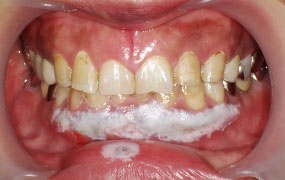

- 歯肉を電気メスで切除する事によって笑った時に歯が見える症状(ガミースマイル)を改善する事を目的とした治療です。

- 治療後

| 治療名(症例) | 歯肉整形(ガミースマイル) |

|---|---|

| 症例 | ガミースマイル |

| 治療本数 | 8本 |

| 治療期間(通院回数) | 1日(2回) |

| 費用 | 4万円+TAX |

| リスク副作用 | ・切除した歯茎が後戻りする可能性があります。 ・術後2週間程は赤みや微出血が生じる場合があります。 ・2~3日は麻酔をした部分が内出血となって、しみたり痛みを伴う場合があります。 |